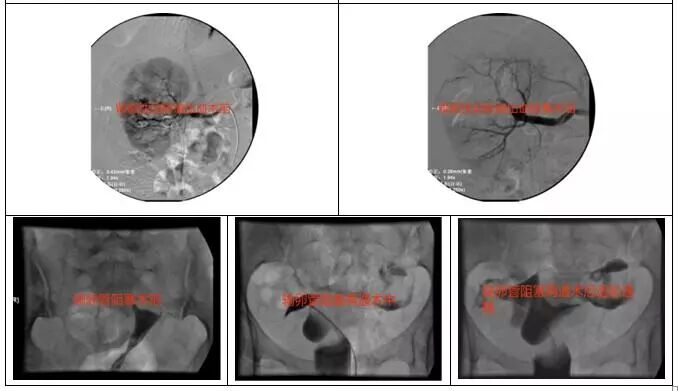

经过术前充分讨论,缜密制定介入手术方案及风险防范控制措施,果断实施手术。术中行腹腔脏器多支血管造影,锁定出血动脉瘤,历经3个多小时的抢救,栓塞止血成功,患者顺利转入普通病房,此时已是晚上10点多。

我院介入放射室主要业务包括血管介入与非血管介入,以肿瘤介入治疗及血管性疾病介入治疗为重点,联合心血管内科、神经外科、心胸外科等重点学科开展冠心病支架置入,脑动脉瘤栓塞,大血管支架置入等多项复杂手术项目。在颈椎病、腰椎间盘突出症置管治疗、射频消融、髓核旋切、臭氧消融等;针对肝癌、肺癌、胰腺癌等恶性肿瘤联合相关学科采用栓塞、灌注、粒子植入、微波消融等多种手段效果确切;针对不宜开放手术或有保留子宫愿望的子宫肌瘤采用子宫动脉栓塞术,针对输卵管阻塞导致不孕的再通术均取得满意效果。